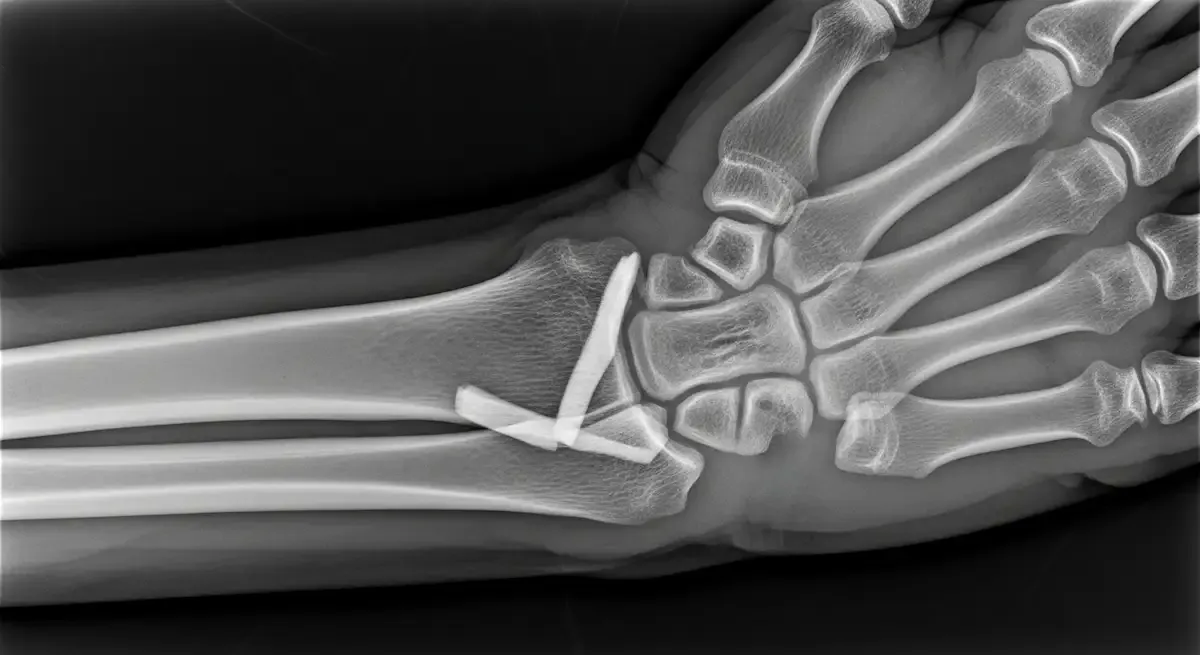

Trata-se de uma fratura intra-articular da base do primeiro metacarpo, na junção com o osso trapézio.

O padrão costuma ser instável pela ação muscular que puxa o fragmento, por isso, o alinhamento correto é decisivo para proteger a cartilagem da articulação carpometacarpal do polegar.

O exame físico identifica a dor localizada e limitação funcional. Radiografias confirmam a fratura de Bennett e avaliam o desalinhamento.

Em casos selecionados, a tomografia ajuda a medir incongruências articulares e planejar o tratamento.

- Redução fechada com fixação percutânea usando fios ou parafusos.

- Redução aberta e fixação interna quando não se obtém alinhamento adequado de modo fechado.